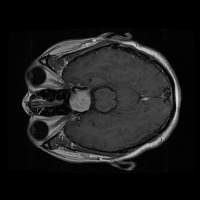

Early Detection of Brain Tumors: Use the "tesis" model to analyze MRI scans of patients proactively during routine check-ups, helping in the early identification of the presence of lesion selar or tumor hipofisario, leading to timely and potentially life-saving interventions.

Assisting in Treatment Planning: Oncologists and neurosurgeons can use the "tesis" model to study the location, size, and class of a patient's tumor. This helps in determining the best treatment options and surgical approaches, ultimately improving patient outcomes.

Medical Education and Training: Incorporate the "tesis" model in medical school curricula and professional trainings aimed at educating future doctors and radiologists about the identification and treatment of lesion selar and tumor hipofisario.

Research Tool for Cancer Studies: The "tesis" model can serve as a tool for researchers working on experimental treatments or clinical trials focused on lesion selar and tumor hipofisario. By identifying tumor classes efficiently and consistently, the model can help researchers compare treatment efficacy and study tumor progression over time.

Second Opinion Provider: Medical professionals can use the "tesis" model to double-check their own findings when analyzing brain MRI scans. This can reduce the likelihood of diagnostic errors and help confirm the presence of lesion selar or tumor hipofisario, resulting in more accurate decision-making.